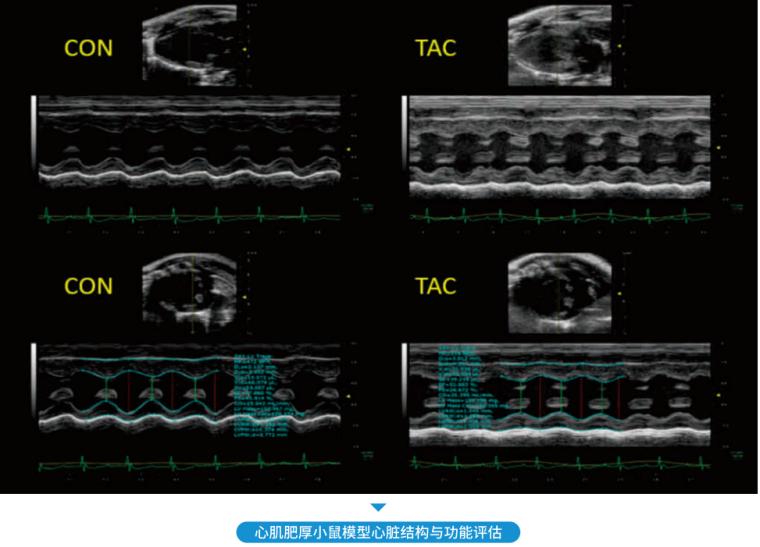

• 超高分辨率小动物超声

超高分辨率小动物超声

心血管系统、全身血管、腹腔、肿瘤研究、发育研究